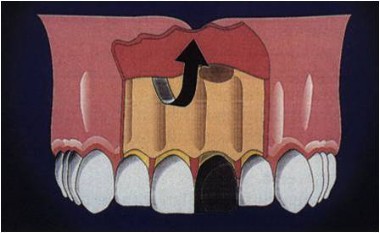

患者一週後回診,已無疼痛等症狀,建議患者以顯微手術清除根尖囊腫,患者的牙尖底部有囊腫(圖六),經翻瓣(圖七)後將根尖囊腫移除(圖八),將牙根尖切除